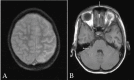

Rasmussen encephalitis is an extremely rare chronic inflammatory neurodegenerative disease affecting a single cerebral hemisphere, causing progressive neurological deterioration and intractable seizures. Imaging plays an important role in diagnosis by demonstrating focal or unihemispheric involvement and excluding other possible causes. Here, we report a case of Rasmussen encephalitis with an update on recent diagnostic criteria and emphasis on differential diagnoses which can be excluded on imaging.